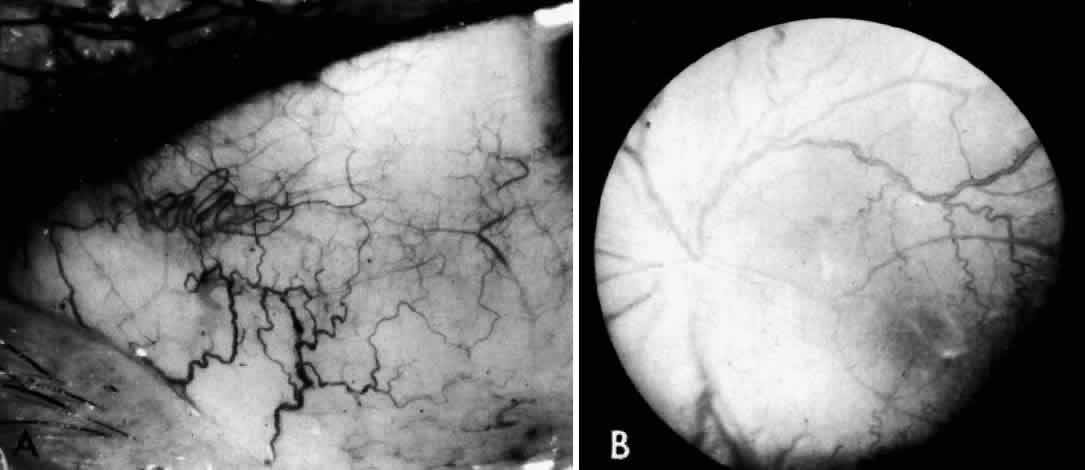

In frozen sections of formalin-fixed retina, both ganglion cells and amacrine cells show marked granular cytoplasmic birefringence. In the study by Robb and Kuwabara68 frozen sections of other portions of the eye revealed a remarkably wide distribution of storage material giving the granular birefringence. Corneal stromal cells were markedly positive, as were corneal endothelium and lens epithelium. The vascular endothelium, the nonpigmented epithelium of the ciliary body, and the retinal pigment epithelium were uniformly birefringent.

Electron microscopic examination of the cornea and retina showed the lipid stored was in the form of membranous cytoplasmic bodies (Fig. 7).68 The distribution of these inclusion bodies is similar to that of the birefringent material seen on light microscopy. The bodies are most abundant in retinal ganglion cells and retinal pigment epithelium. They are present in moderate numbers in corneal stromal cells, lens epithelium, corneal endothelium, vascular endothelium, and the sphincter muscle of the iris. They are infrequent in Müller cells, glial cells, and rod and cone inner segments.

Fig. 7. Retinal ganglion cell. (A) Portion of cell in Niemann-Pick disease, showing numerous membranous cytoplasmic bodies. Mitochondria (m) and dilated endoplasmic reticulum (er) are also evident. Area outlined in lower right is shown in greater magnification in B. (× 15,000) (B) Portion of cytoplasm of ganglion cell shown in A. Membranous cytoplasmic bodies cut in several different planes are evident, as are mitochondria (m) and endoplasmic reticulum (er) (×42,000). (Robb RM, Kuwabara T: The ocular pathology of type A Niemann-Pick disease: A light and electron microscopic study. Invest Ophthalmol 12:366, 1973)

The morphology of the membranous cytoplasmic bodies found in the eye in Niemann-Pick disease type A corresponds closely to the previously reported ultrastructure of lipid inclusions in the brain and viscera in other patients with Niemann-Pick disease type A. An ocular ultrastructural study of a 23-week-old fetus with Niemann-Pick disease type A also demonstrated rather extensive ocular involvement.69